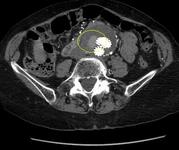

Fuga interna de tipo II (rodeada) descubierta en tomografía computarizada de seguimiento

University of Michigan, específicamente los casos del Dr. Upchurch que reflejan los Departamentos de Cirugía Vascular y Radiología